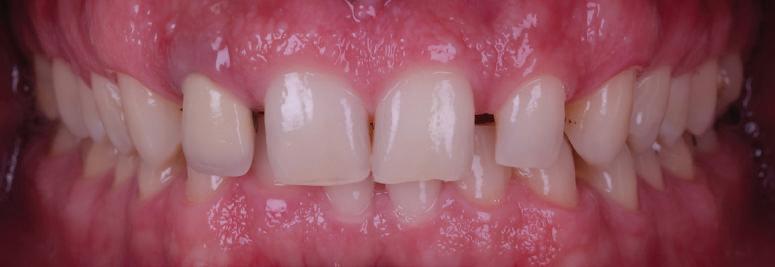

11Dental Tribune Bulgarian Edition / октомври 2022 г. Преди лечението Фиг. 1 Фиг. 2 Фиг. 3 Фиг. 4 Фиг. 5 Фиг. 6 Фиг. 7 Фиг. 9 Фиг. 10 Фиг. 11 Фиг. 8 Фиг. 12 Фиг. 13

12 Dental Tribune Bulgarian Edition / октомври 2022 г. По време на лечението Фиг. 14 Фиг. 16 Фиг. 20 Фиг. 23 Фиг. 21 Фиг. 24 Фиг. 26 Фиг. 28 Фиг. 31 Фиг. 34 Фиг. 29 Фиг. 32 Фиг. 35 Фиг. 30 Фиг. 33 Фиг. 36 Фиг. 27 Фиг. 22 Фиг. 25 Фиг. 17 Фиг. 18 Фиг. 19 Фиг. 15

13Dental Tribune Bulgarian Edition / октомври 2022 г. След лечението За авторите: Д-р Калин Маринов е специалист в областта на имплантологията, протетиката и естетичната хирургия. Завършил е дентална медици на в София през 2012 г. През 2014 г. основава Sky Dental Clinic. Бил е на обмен ни начала в катедра „Протетика“ на Университета по дентална медицина във Фрайбург, Германия. Живял е и е практикувал в Мелбърн, Австралия, и е посеща вал курсове и лекции в Италия, Швейцария, Германия с насоченост в естетич ната хирургия и имплантология, както и тоталната рехабилитация на устна та кухина чрез импланти. Зт. Стефан Петров основава собствена лаборатория през 2006 г. Официален демонстратор на GC за България, като от 2015 г. е KOL за Източна Европа. Инструктор е на Straumann за България. Лаборатория та му има сертификат за пилотна лаборатория на Micerium – Италия. Носител е на множество награди в денталния конкурс „Усмивка на годината”. Носител е на награда CERAMISTS MASTER CUP с д-р Софиен Риахи в престижния международен конгрес CERAMISTS – NO LIMITS 2015 г. Изнася лекции и провежда курсове в редица европейски страни. Фиг. 37 Фиг. 40 Фиг. 43 Фиг. 45 Фиг. 47 Фиг. 50 Фиг. 48 Фиг. 49 Фиг. 41 Фиг. 44 Фиг. 46 Фиг. 42 Фиг. 38 Фиг. 39